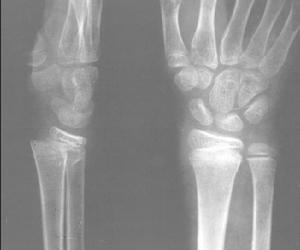

橈骨頸骨折診斷檢查

除外傷史及臨床症狀外,主要依據X線平片確診及分型。分析影響學所見,一般分為以下四型:

1.無移位型:指橈骨頸部的裂縫及青枝骨折,此型穩定,一般勿需復位。多見於兒童。

2.嵌頓型:多系橈骨頸骨折時遠側斷端嵌入其中,此型亦較穩定。

3.歪戴帽型:即橈骨頸骨折後,橈骨頭部骨折塊偏斜向一側,猶如人戴法蘭西帽姿勢。

4.粉碎型:指橈骨、頸及(或)頭部骨折呈三塊以上碎裂者。